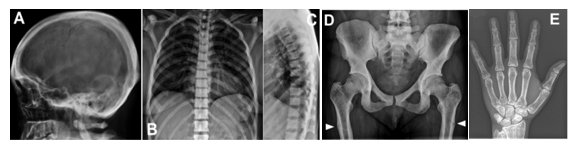

頭蓋骨、脊椎、骨盤、大腿骨の骨濃度の増加が見られる、Ikegawa型大理石骨病患者のX線像

図1 Ikegawa型大理石骨病のX線像

新たなタイプの大理石骨病(Ikegawa型大理石骨病)患者のX線像。A:頭蓋骨は幅が厚い。B, C:脊椎は一様に骨濃度が上昇している。D:骨盤、大腿骨の骨濃度の増加。白矢印は、大腿骨の偽骨折。E: 手の短管骨の皮質は幅が厚い。